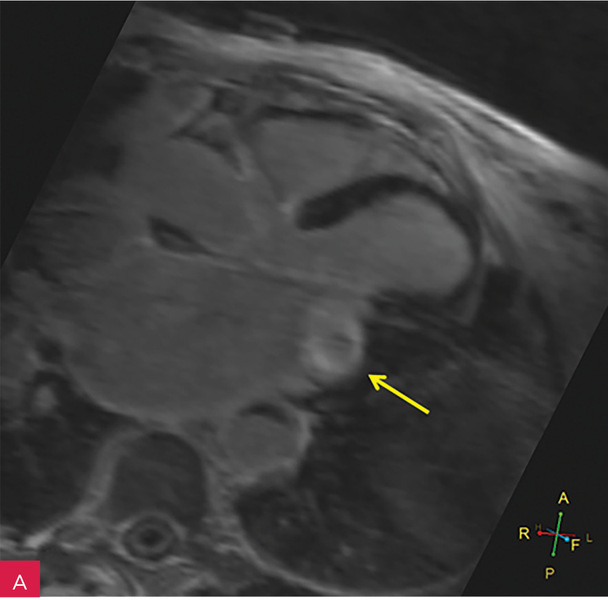

Rycina 7A-D. Obrazy rezonansu magnetycznego w osi krótkiej na wysokości pierścienia mitralnego: czarnej krwi T1-zależne TSE (A); czarnej krwi T2-zależne HASTE (B); T1-zależne echa gradientowego dynamicznie podczas podawania środka kontrastowego (C); sekwencja SSFP, pojedynczy obraz w osi krótkiej (D). W dolno-bocznej części pierścienia mitralnego od strony światła lewej komory zmiana (strzałki) niskosygnałowa we wszystkich ważeniach sygnału

W celu weryfikacji zmiany i oceny charakterystyki tkanki wykonano CMR,

w którym stwierdzono w dolno-bocznej części pierścienia mitralnego od strony światła lewej komory zmianę odpowiadającą morfologicznie CCMA, obejmującą 7,3 cm obwodu pierścienia mitralnego, o grubości w osi krótkiej do 25 mm, w osi długiej do 21 mm; zmiana ulegała brzeżnemu wzmocnieniu kontrastowemu i powodowała ograniczenie ruchomości tylnego płatka zastawki mitralnej, obejmowała struny ścięgniste mięśnia brodawkowatego tylno-przyśrodkowego. Ponadto uwidoczniono znacznie powiększone przedsionki z istotnym włóknieniem – jak w restrykcji (ryc. 7, 8).